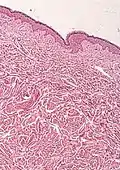

- Histological test